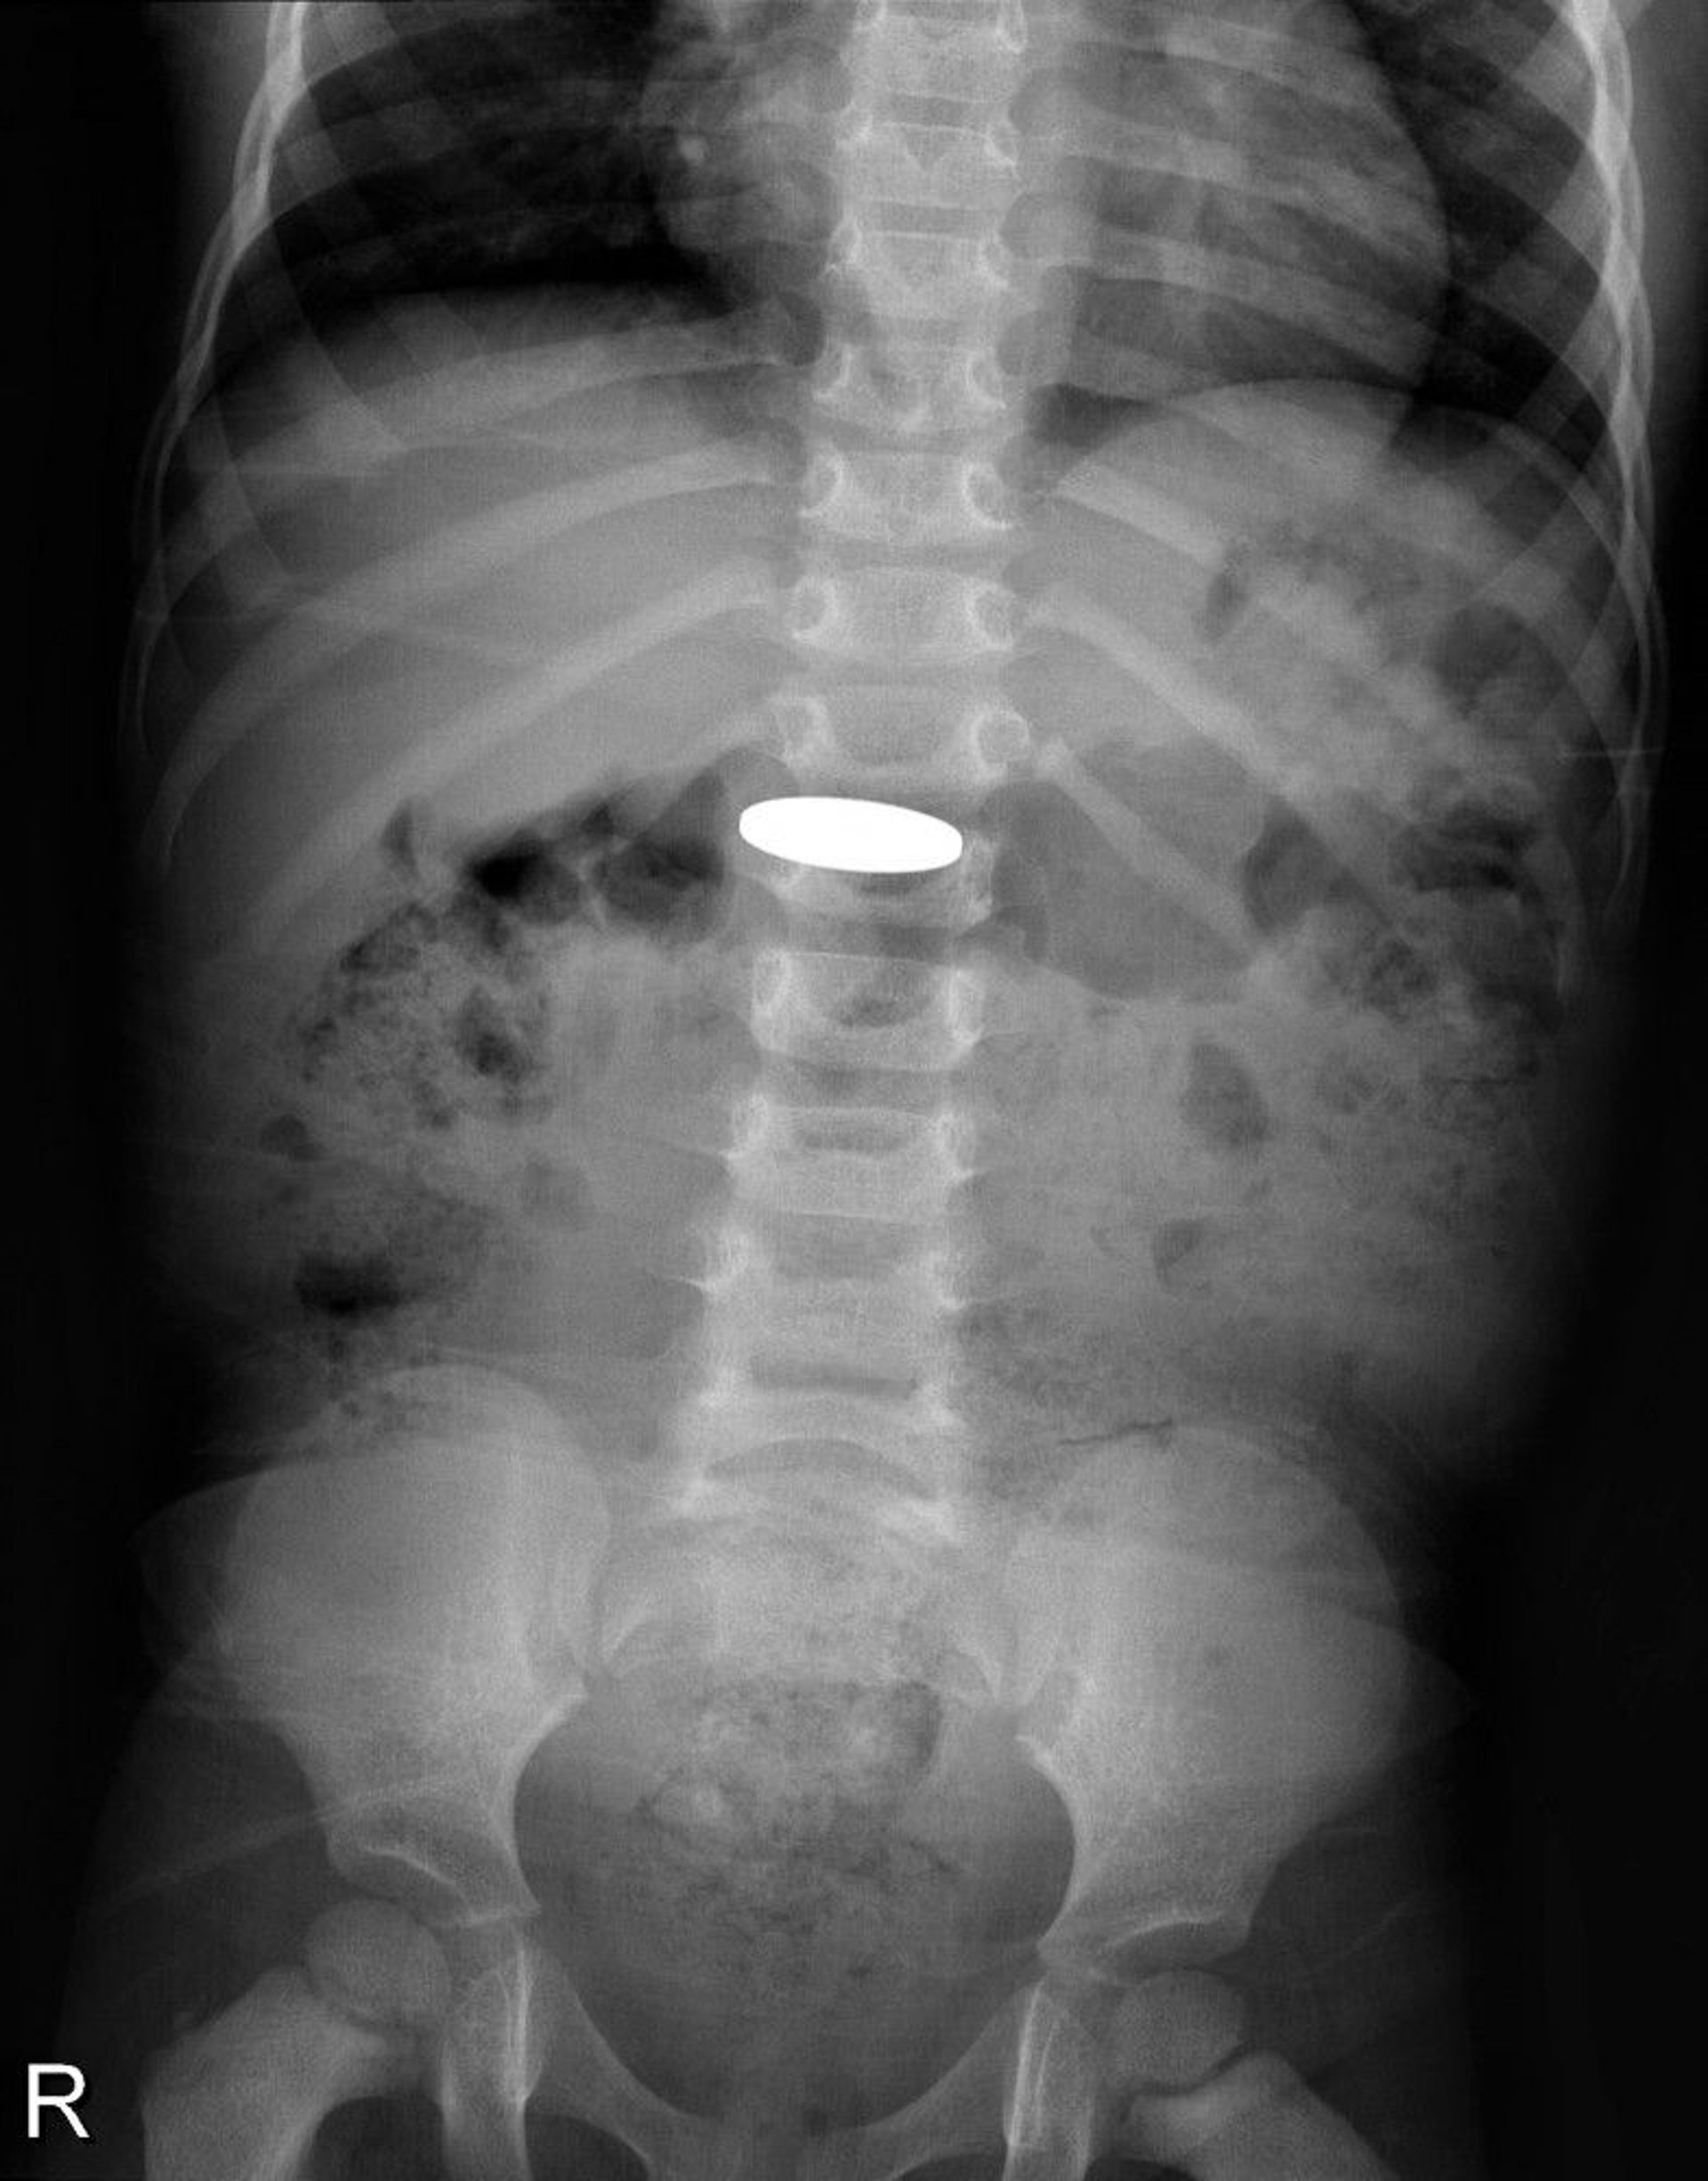

Benda Asing di dalam Saluran Pencernaan (Sinar-X)

Sinar-x ini menunjukkan koin yang ditelan oleh anak kecil.